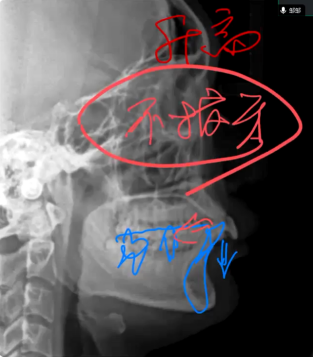

低角深覆盖患者面下三分之一较短,在正畸内收过程中要增加垂直向高度,需要下前牙的整个牙轴向远中往里直立内收,同时下前牙要压低,双尖牙要升高。

不拔牙是低角深覆盖的正畸要点,改善前牙深覆盖,维持后牙咬合关系。